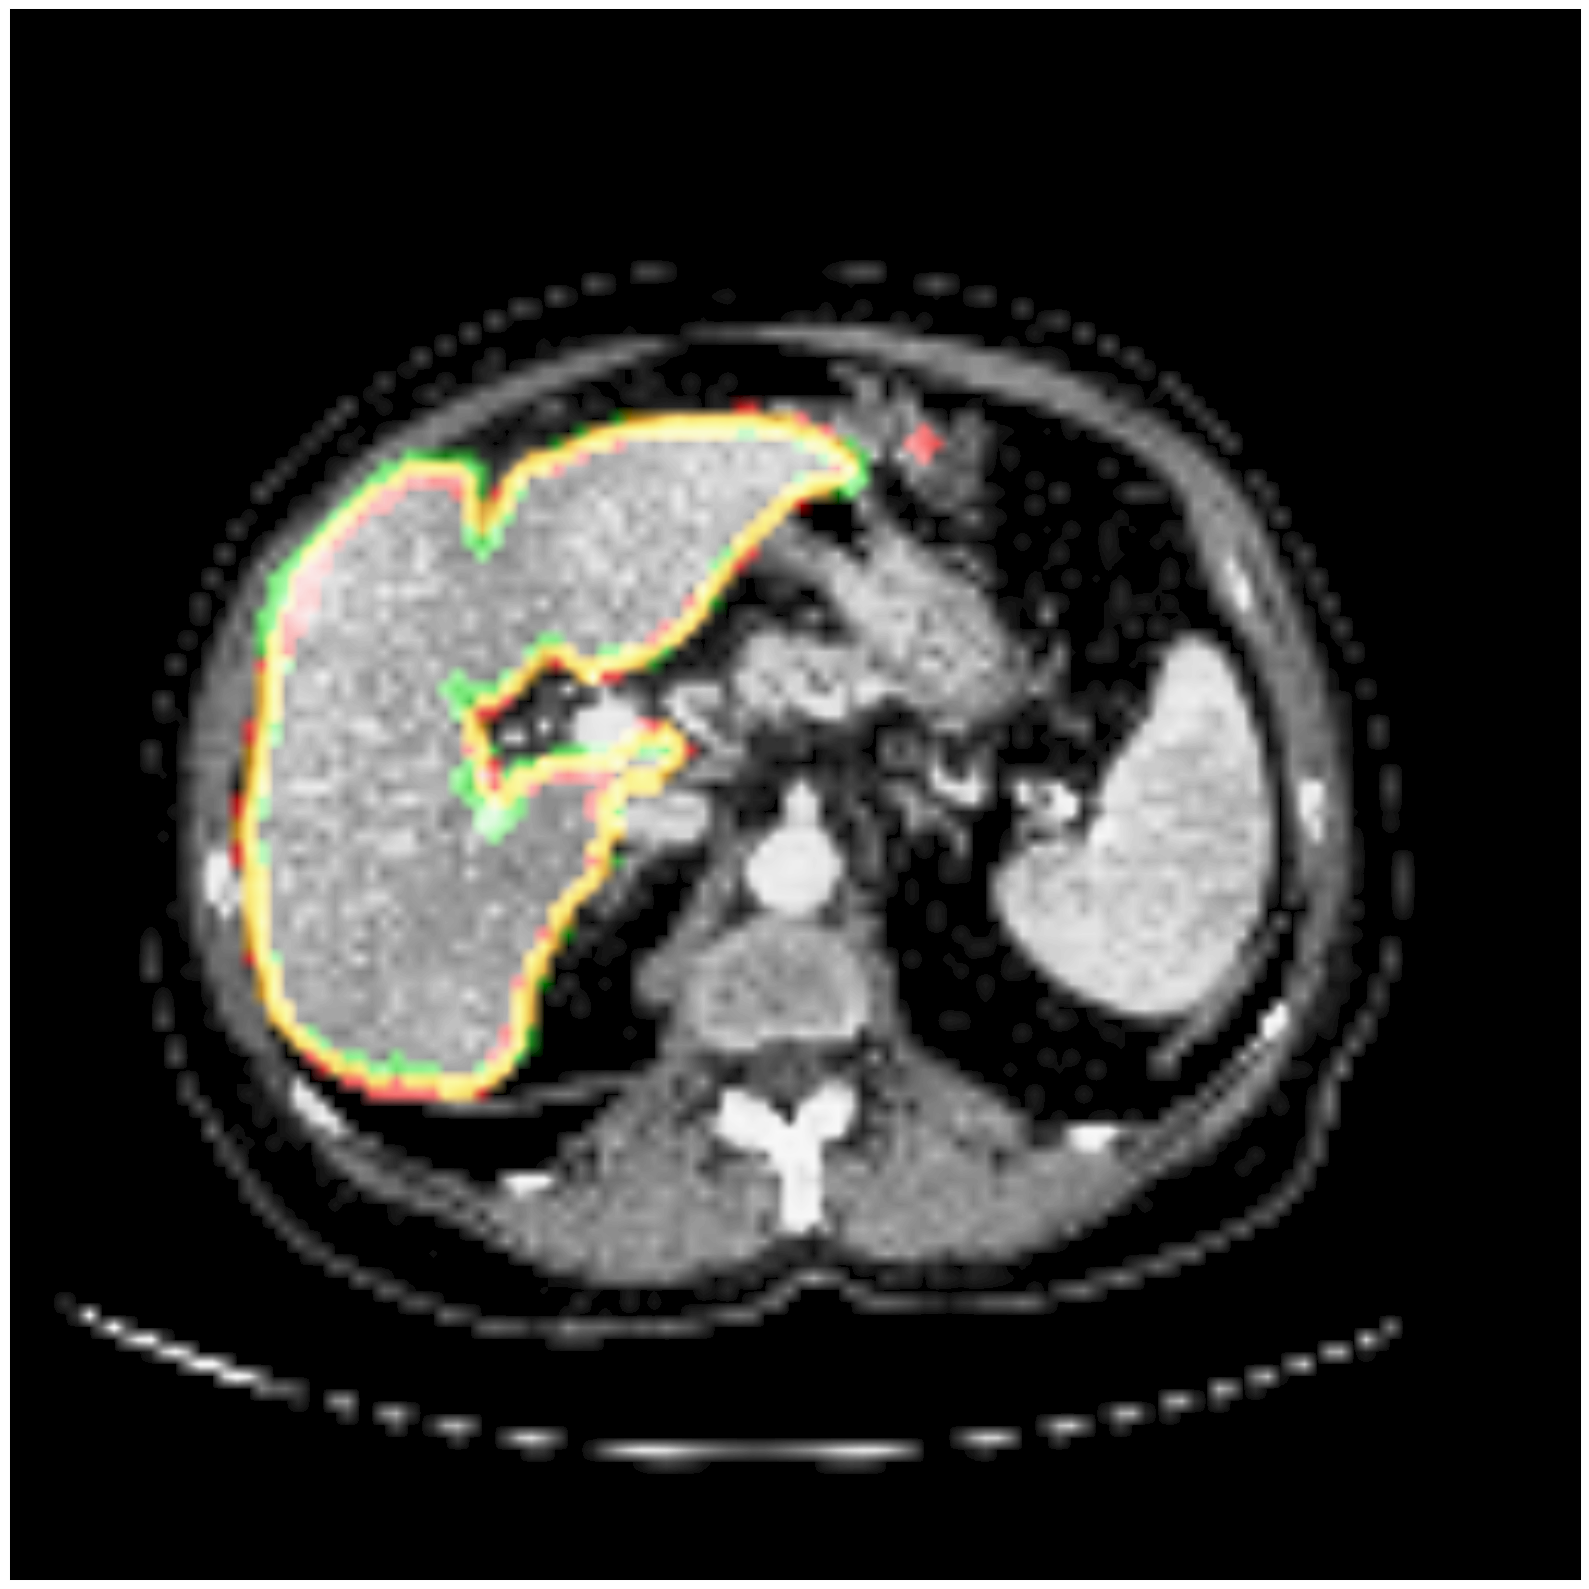

Some segmentation results at different vertebrae (top) and liver (bottom) areas are depicted in Fig. 2. The red contour corresponds to the outline of the prediction, green to the ground-truth and yellow to the overlap of the outlines.